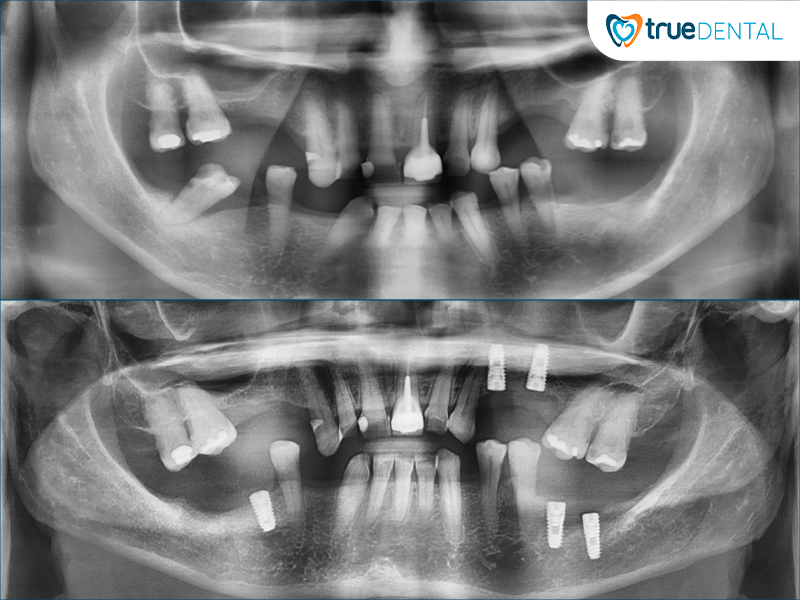

Công nghệ chụp CBCT và xét nghiệm miễn phí: Để đảm bảo độ chính xác và an toàn cao nhất cho khách hàng, tại trueDental, Cô Chú được chụp CBCT (chụp X-Quang) giúp bác sĩ quan sát rõ ràng cấu trúc xương hàm và tình trạng bên trong hàm. Cô Chú được miễn phí toàn bộ các xét nghiệm cần thiết và nhận phát đồ điều trị chuyên môn chính xác trước khi tiến hành cắm Implant.